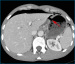

Abbildung 3: Lungenfenster Die Rekonstruktion der CT-Bilder im sogenannten "Lungenfenster" zeigt anschaulich die Luftansammlungen in der Peritonealhöhle. Das Ligamentum falciforme der Leber ist von Luft umgeben (Pfeile). |

Die Rekonstruktion der CT-Bilder im sogenannten "Lungenfenster" zeigt anschaulich die Luftansammlungen in der Peritonealhöhle. Das Ligamentum falciforme der Leber ist von Luft umgeben (Pfeile). |